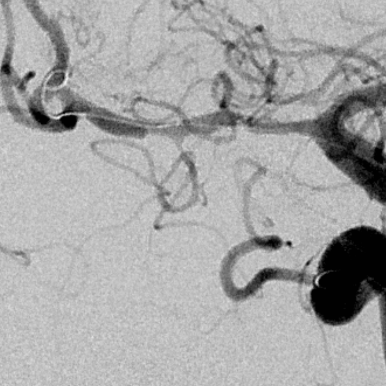

半小时后发现近端出现夹层,决定支架植入

确认为夹层,直接支架植入

远端似乎打开不好,由于确认了为夹层,后面支架会进一步打开,无需过多操作,进一步球扩可能会导致高灌注,因为MCA远端的上干已经闭塞,只有下干,手术保留豆纹动脉的通畅为重点

支架进一步打开,直径改善到2.9mm

进一步打开的支架的形态,打开满意